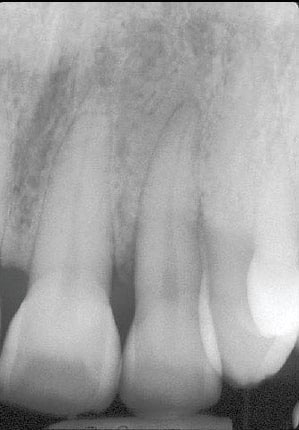

A. If you have been told that you have gum disease, notice that your teeth have any mobility, or your gums bleed when you brush and floss, you will need periodontal therapy (gum treatment) and likely TPT would be a great option for you. A thorough consultation with a complete set of x-rays in conjunction with a review of your medical and dental history will be necessary to advise you on the proper treatment options.